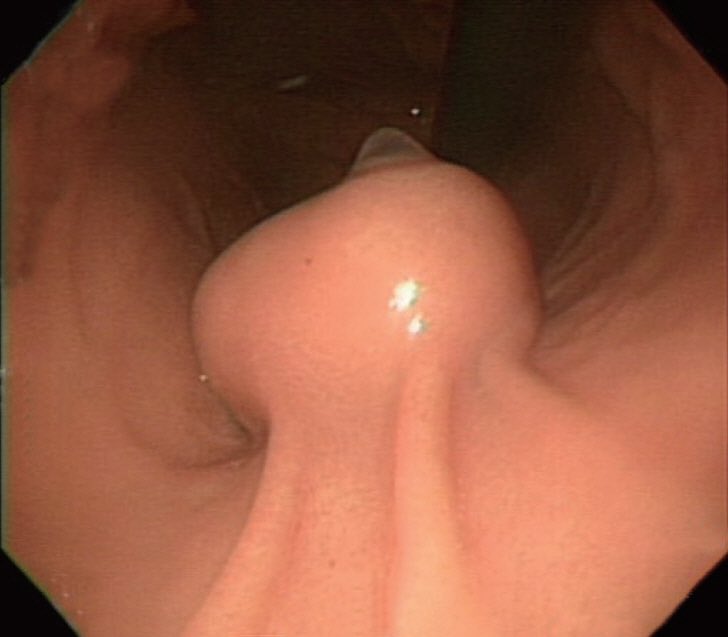

عادة ما تكتشف بالصدفة اثناء اجراء منظار للمعدة دون وجود اي اعراض. تظهر على شكل نتوء املس في اجزاء المعدة و ذو احجام متفاوتة. في بعض الحالات قد تنتج الأعراض بسبب زيادة الحجم مسببة انسداد او فقدان للشهية مصحوب بألم او على شكل نزيف إذا ما تقرحت اجزاء من الورم.